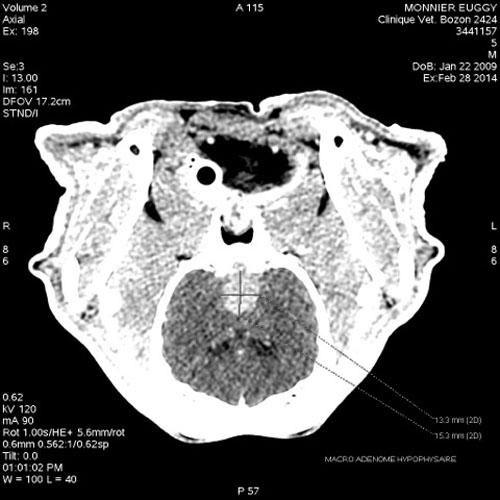

• Scanner (réalisé par la Clinique Vétérinaire Bozon à Versailles) : (photos)

• Mise en évidence d’un volumineux macroadénome hypophysaire de 19,2 x 15,3 x 13,3 mm